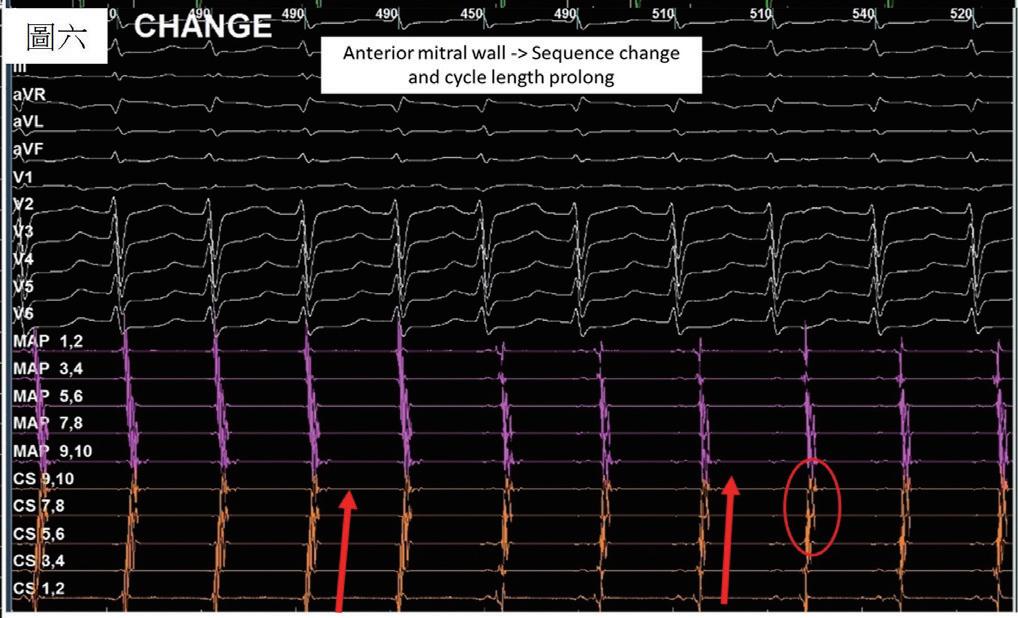

一位 76 歲女性,有高血壓以及陣發性心房顫動病史,規律於心臟科門診服用抗心律不整藥物 (flecainide) 以 及抗凝血劑 (apixaban) 以控制慢性病。然而,病人最近數月來感到間歇性胸悶與心悸,且症狀逐漸加重。經血 管介入專家排除冠狀動脈狹窄阻塞之問題後,判斷此病人之不適與多種嚴重心律不整有關 ( 如圖一與圖二 ) ,包 含可能源自於左心房的心房撲動 (atypical atrial flutters) 。經詳細解釋與討論,病人決定入院接受電氣生理檢查 與電氣燒灼治療。術前電腦斷層顯示左心房及左心耳無血栓,左心房有擴大 ( 約為 160 毫升 ) 。手術當日,病人心 律為 counter-clockwise isthmus-dependent atrial flutter( 如圖三 ) ,利用 entrainment method ,冠狀竇近端比遠端更 近 flutter circuit , 3 維傳播路徑圖為逆時針旋轉路徑。但是在 cavo-tricuspid isthmus 阻斷後, flutter 並未停止,發 生了訊號序列以及 cycle length 的變化,此時右側心房沒有辦法找到合適 entrainment 位置,經兩心房 3 維傳播路 徑圖判定病人之心律不整已轉變為源自左心房後壁之 atypical atrial flutter ,但是在左心房後壁阻斷後, flutter circuit 和 cycle length 仍不斷改變。在左心房經歷如同警匪追逐戰一般的多次阻斷以及訊號序列轉變後 ( 如圖四至 圖六 ) ,終於在冠狀竇 (coronary sinus) 遠端完成此病人的心律不整電氣燒灼手術 ( 如圖七 ) ,且無法再誘發。此病 人之心房撲動訊號序列變化與燒灼相關整理如圖八。術後病人恢復良好,胸悶心悸感已完全消除,固定於門診 領取抗凝血劑與低劑量抗心律不整藥物持續服用併追蹤。

(圖六)、 Mapping後判斷轉為mitral flutter,於是先 針對anterior mitral line進行電燒。然而在 電燒過程中,訊號再次出現細微變化, CS 7,8,9,10出現一些碎裂分岔的訊號。